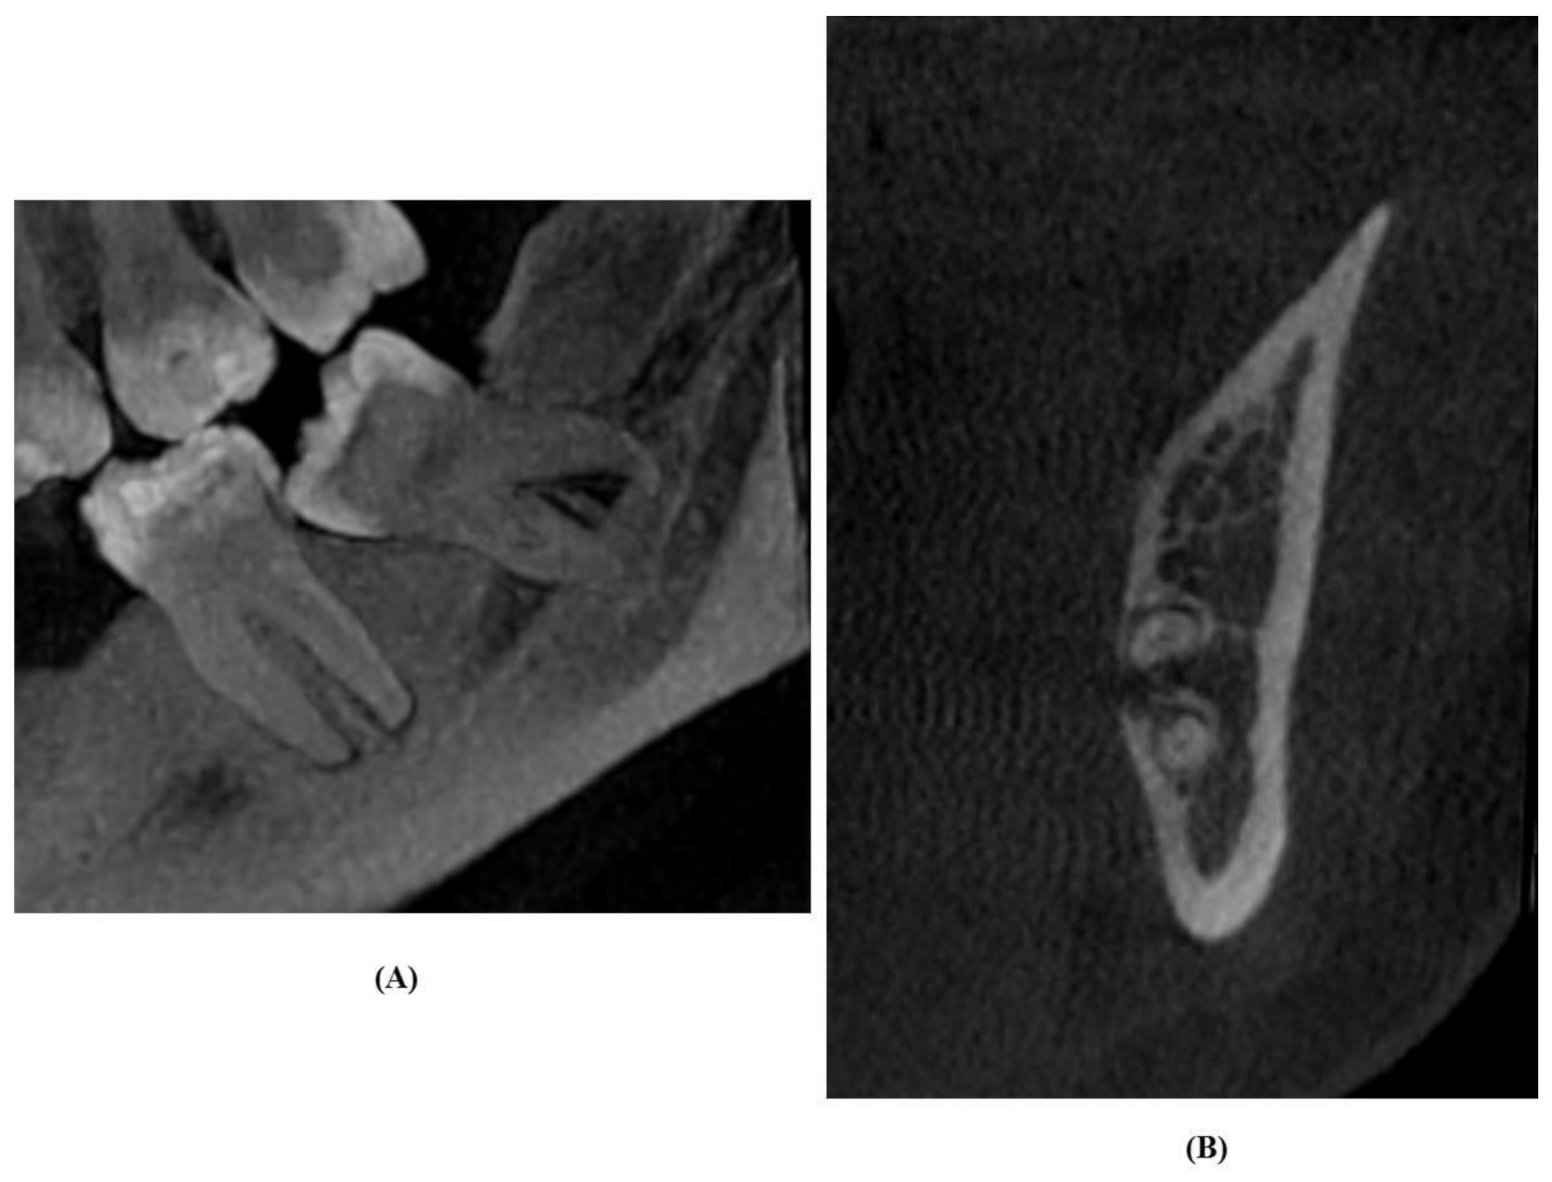

2.4. Evaluation of OPG Images

2.5. Analysis of CBCT Images